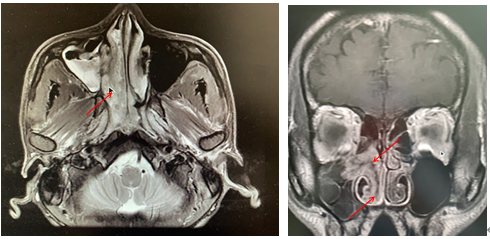

患者李某,男性,42岁,于4月前无明显诱因出现右侧鼻塞,流清涕、打喷嚏,伴咽干咽痛、口干口苦。入院前2天曾在当地医院检查发现右侧鼻腔肿物,建议手术治疗。患者随后在我院耳鼻喉科就诊,收治入院后查副鼻窦CT提示:右侧鼻道内软组织密度块影,病变累及鼻咽部、右侧上颌窦及右半筛窦。进一步完善副鼻窦核磁平扫+增强+DWI提示:右侧鼻腔内异常信号并向鼻咽腔及右侧上颌窦腔内延伸,结合强化,多考虑肿瘤性病变,内翻性乳头状瘤可能。术前病检回报示:(右侧鼻腔)内翻性乳头状瘤。诊断明确后,由科主任江燕主刀、在麻醉手术科主任医师谭萍的全力配合下,耳鼻喉科团队为患者成功施行全麻下“鼻内窥镜下右侧鼻腔鼻窦肿瘤切除+右侧上颌窦开放术”,术中完整切除患者右侧鼻腔鼻窦肿瘤,术后恢复良好。

术前副鼻窦增强MRI提示右侧鼻腔、鼻咽部及上颌窦内内翻性乳头状瘤可能